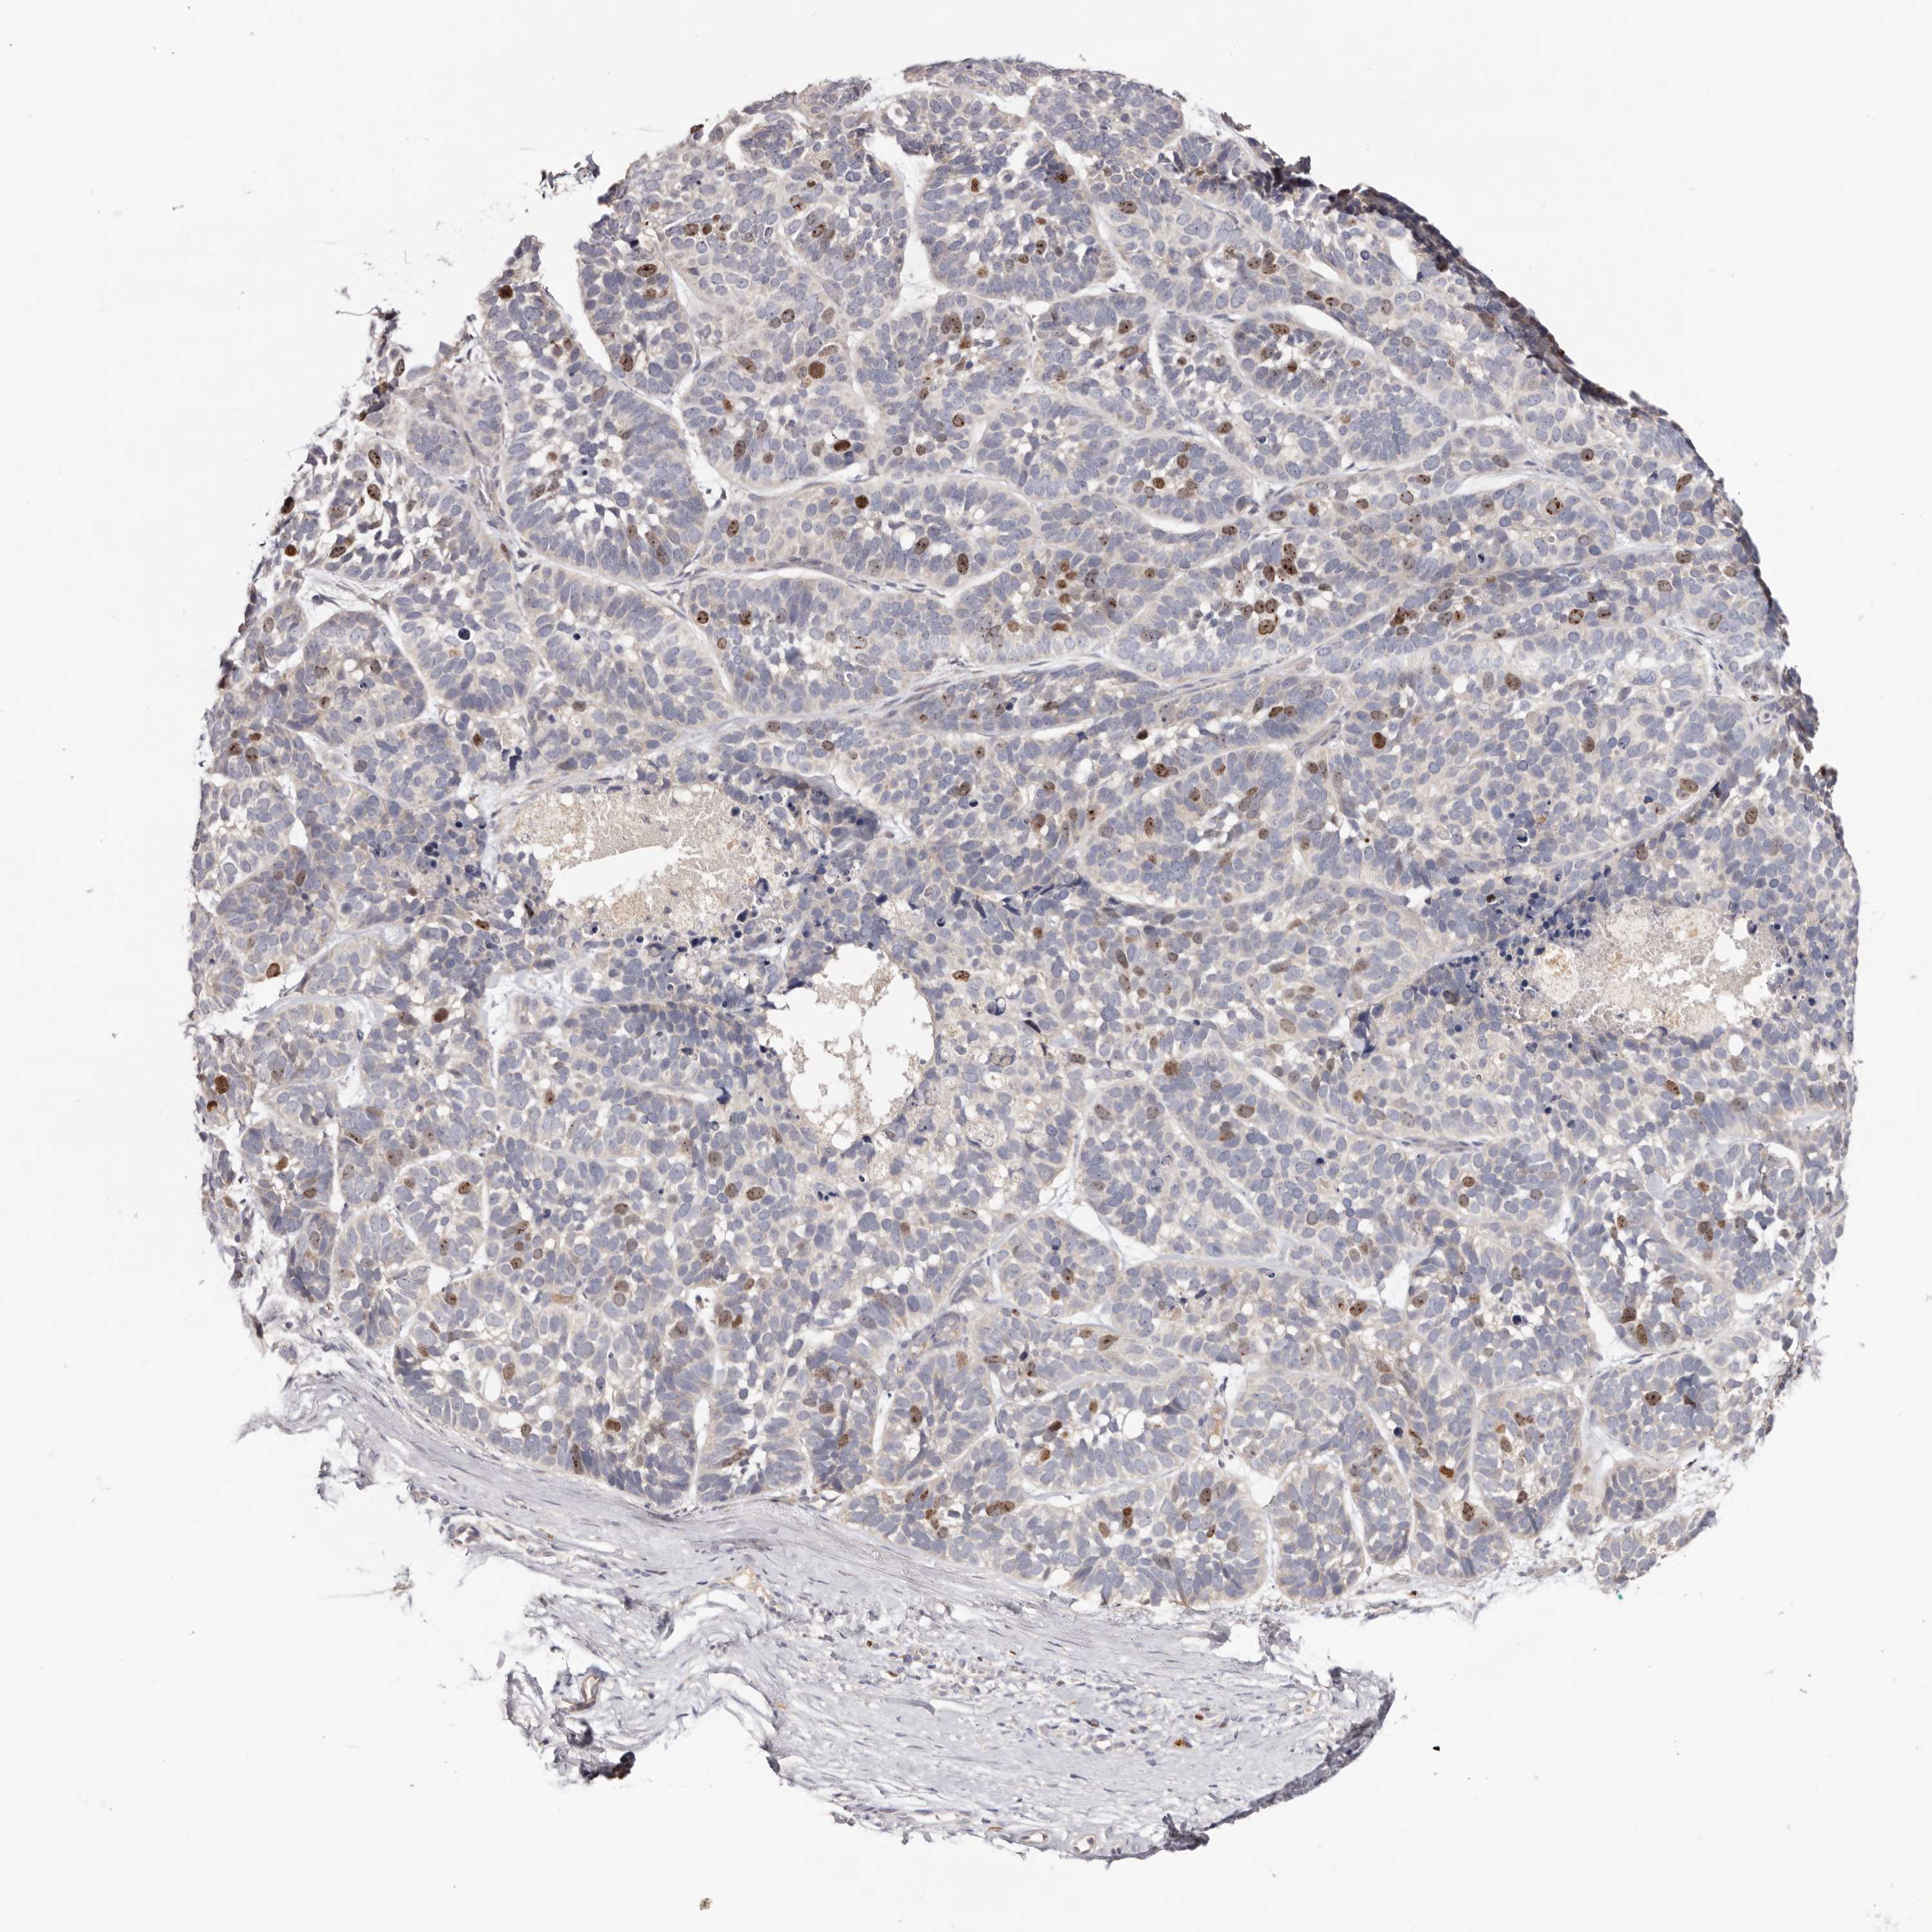

SKIN CANCER - Protein expressioni

A mouse-over function shows sample information and annotation data. Click on an image to view it in a full screen mode. Samples can be filtered based on level of antibody staining by selecting one or several of the following categories: high, medium, low and not detected. The assay and annotation is described here.

Each image is clickable and will lead to virtual microscopy that enables deeper exploration of all samples and also displays staining intensity scores, fraction scores and subcellular localization as well as patient and tissue information for each sample.

Antibody HPA028584

Staining

High

Medium

Low

Not detected

Intensity

Strong

Moderate

Weak

Negative

Quantity

>75%

75%-25%

<25%

None

Location

Nuclear

Cytoplasmic/membranous

Cytoplasmic/membranous,nuclear

Squamous cell carcinoma, NOS

Squamous cell carcinoma, metastatic, NOS